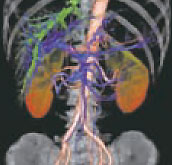

腹部の3D画像

血管や骨・臓器などを、様々な方向の断面で表示させたり画像を立体化(3D画像)させて表示します。

64列マルチスライスCT(GE Optima CT660)